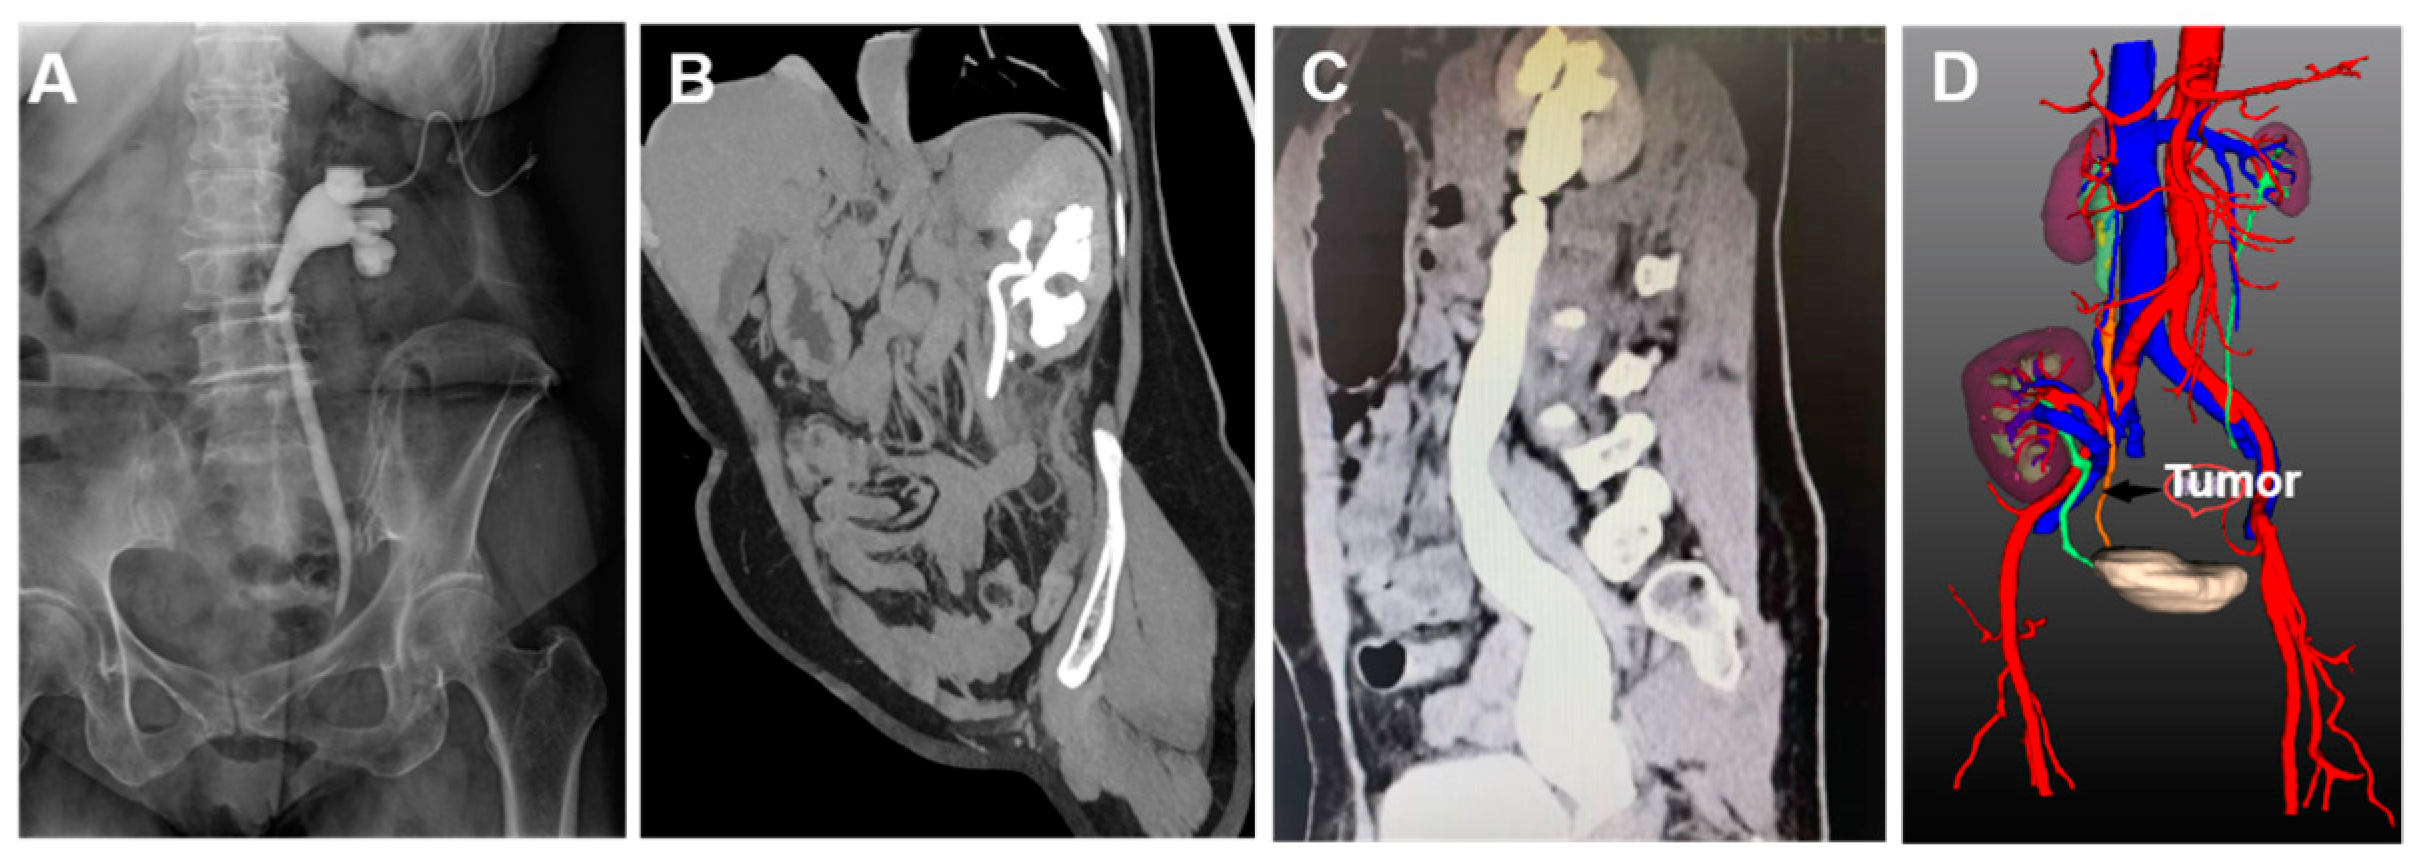

| 14 | Female | 56 | Ipsilateral native ureteral tumor after renal transplantation | Right | - |

| 14 | Native ureterectomy | 169 | 140 | 43 | - | 10 | - |